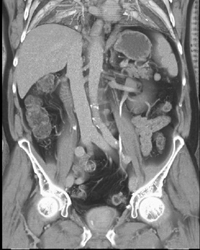

Vascular Renal Cell Carcinoma (RCC)